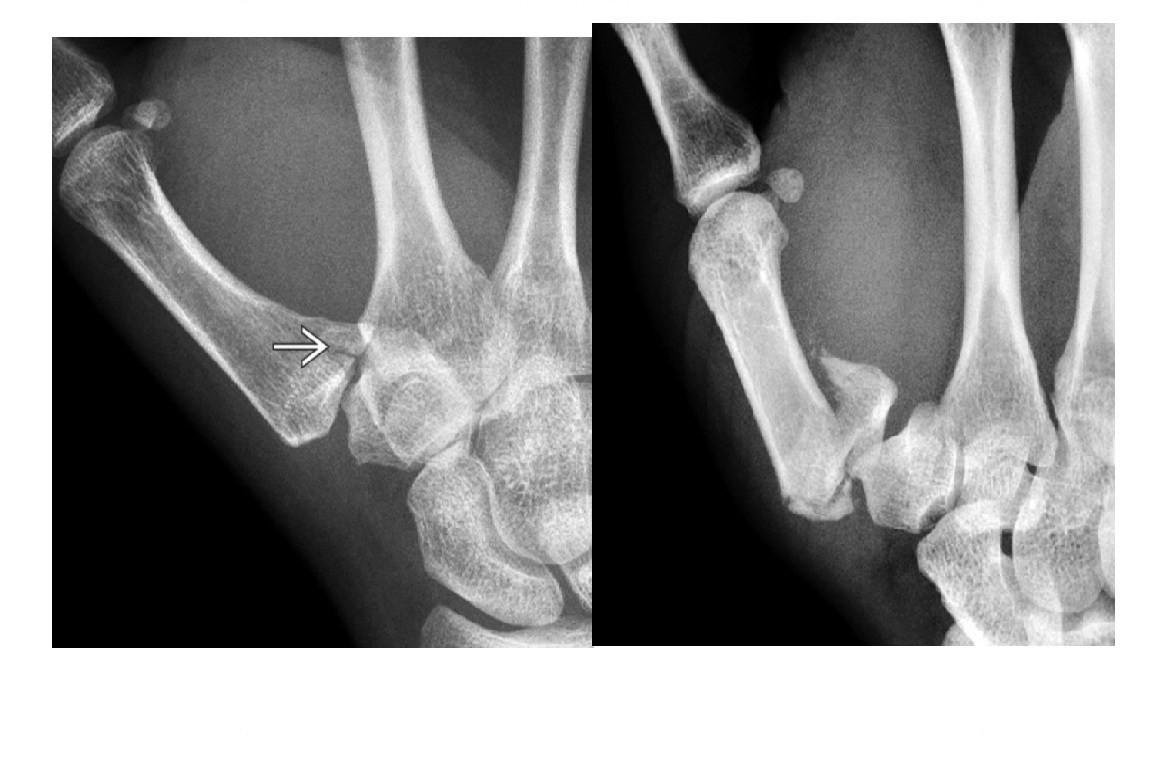

Gamekeepers

Avulsion fracture of the base of the proximal first phalanx

Ulnar collateral ligament disruption

STENER lesion = when adductor tendon gets caught in the torn edges of the UCL = Surgery